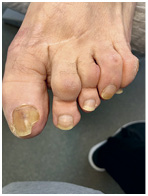

Иллюстрация к книге — Подология понятно. Важен каждый шаг. Справочник по проблемам подологии для клиентов и мастеров эстетики [i_269.jpg]

Иллюстрация к книге — Подология понятно. Важен каждый шаг. Справочник по проблемам подологии для клиентов и мастеров эстетики [i_270.jpg]

Результат работы за 5 месяцев: подолог использовал крючковые коррекционные системы, а хирург сделал пластику внутреннего бокового валика (из-за хронических воспалений боковой валик стал гипертрофированным и давил на ноготь, от чего клиент испытывал постоянный дискомфорт)